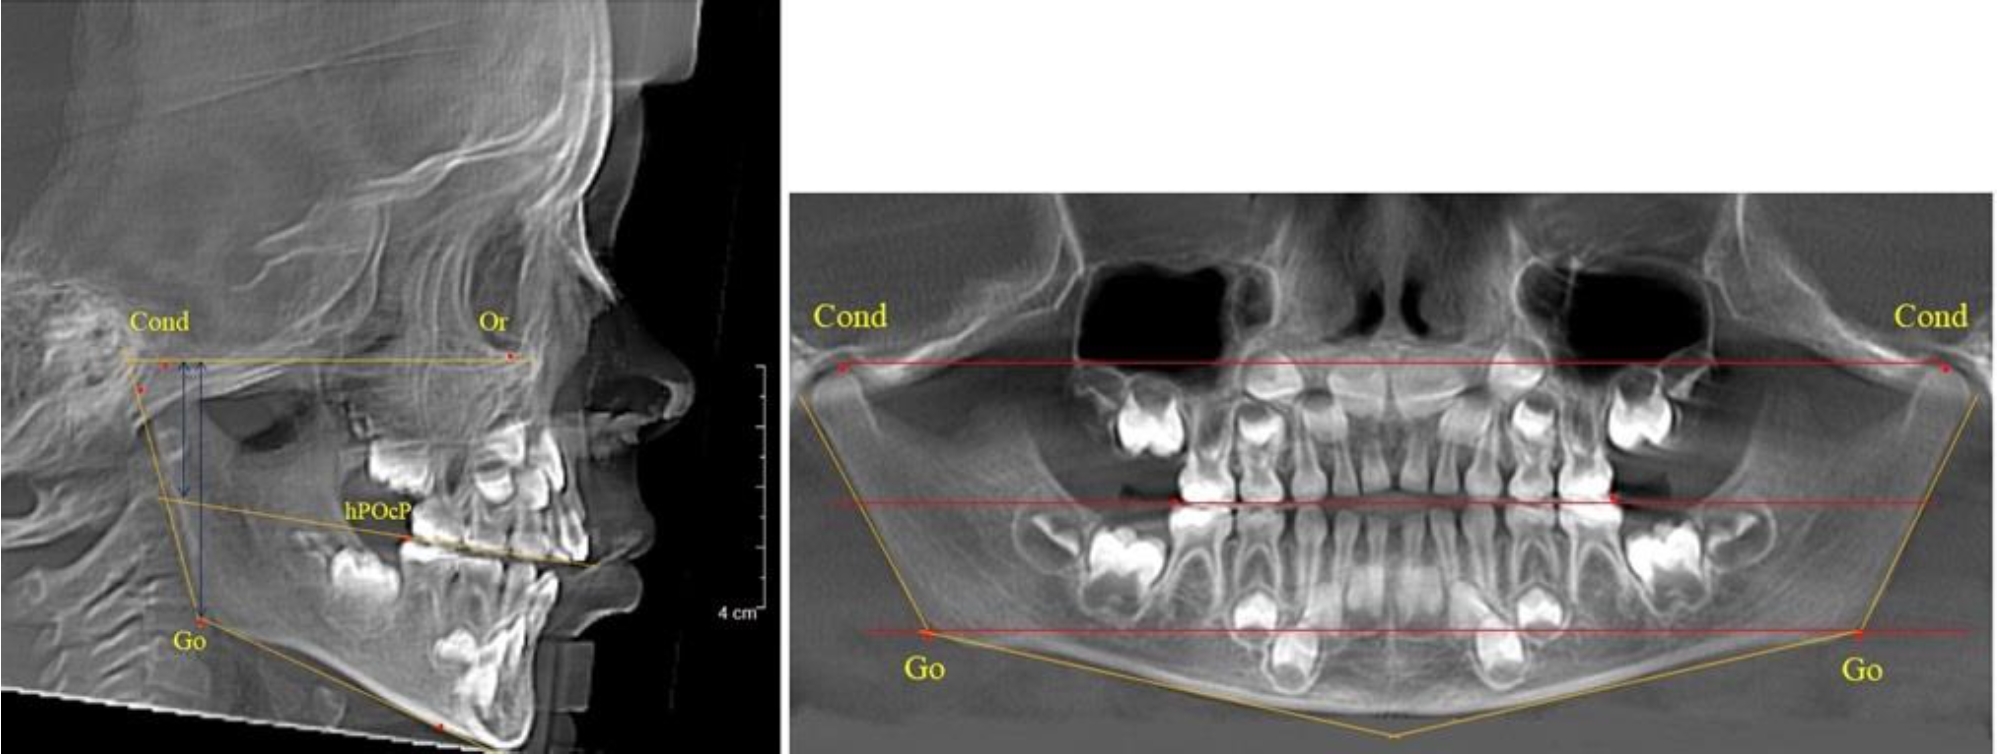

В 4-й группе были проанализированы 12 комплектов рентгенограмм, что составило (11,32 ± 3,08) % от общего числа. На всех рентгенограммах произошла полная смена всех молочных зубов постоянными. Окклюзионная линия делила ветвь на два отдела (рис. 4).

Рис. 4. ТРГ пациента после смены всех молочных резцов

В 5-й группе были проанализированы 14 комплектов рентгенограмм, что составило (13,21 ± 3,29) % от общего числа. На всех рентгенограммах отмечен очередной этап подъема высоты прикуса, обусловленный прорезыванием вторых постоянных моляров. Окклюзионная линия делила ветвь на два отдела (рис. 5).

Рис. 5. ТРГ и ОПТГ пациента после смены молочных зубов и прорезывания вторых постоянных моляров

Высота ветви у детей 5-й группы составляла (62,87 ± 3,62) мм, что было достоверно больше, чем у детей других групп (р ˂ 0,05). При этом высота верхней окклюзионно-суставной части была (40,23 ± 2,01) мм, а нижней – (22,64 ± 1,78) мм. Высота верхней части была вдвое больше нижней, что и определяло особенности соразмерности частей ветви нижней челюсти в анализируемый возрастной период.

Относительные показатели соразмерности частей ветви нижней челюсти показали, что отношение высоты верхней части ветви к нижней в среднем составляло 1,78 ± 0,18. Отношение общей высоты ветви к верхней ее части составляло 1,56 ± 0,12, а отношение общей высоты ветви к нижней ее части было 2,78 ± 0,14, что и определяло особенности соразмерности частей ветви нижней челюсти в анализируемый возрастной период.